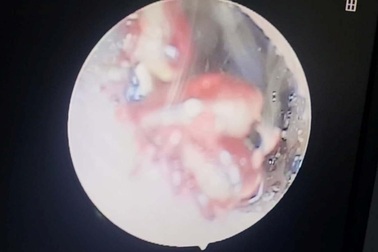

Gắp 4 con ve chó trong tai bé gái 10 tuổiBé gái 10 tuổi thường xuyên ngứa tai, khó ngủ nên được gia đình đưa vào bệnh viện kiểm tra. Bác sĩ phát hiện 4 con ve chó trong tai trẻ.